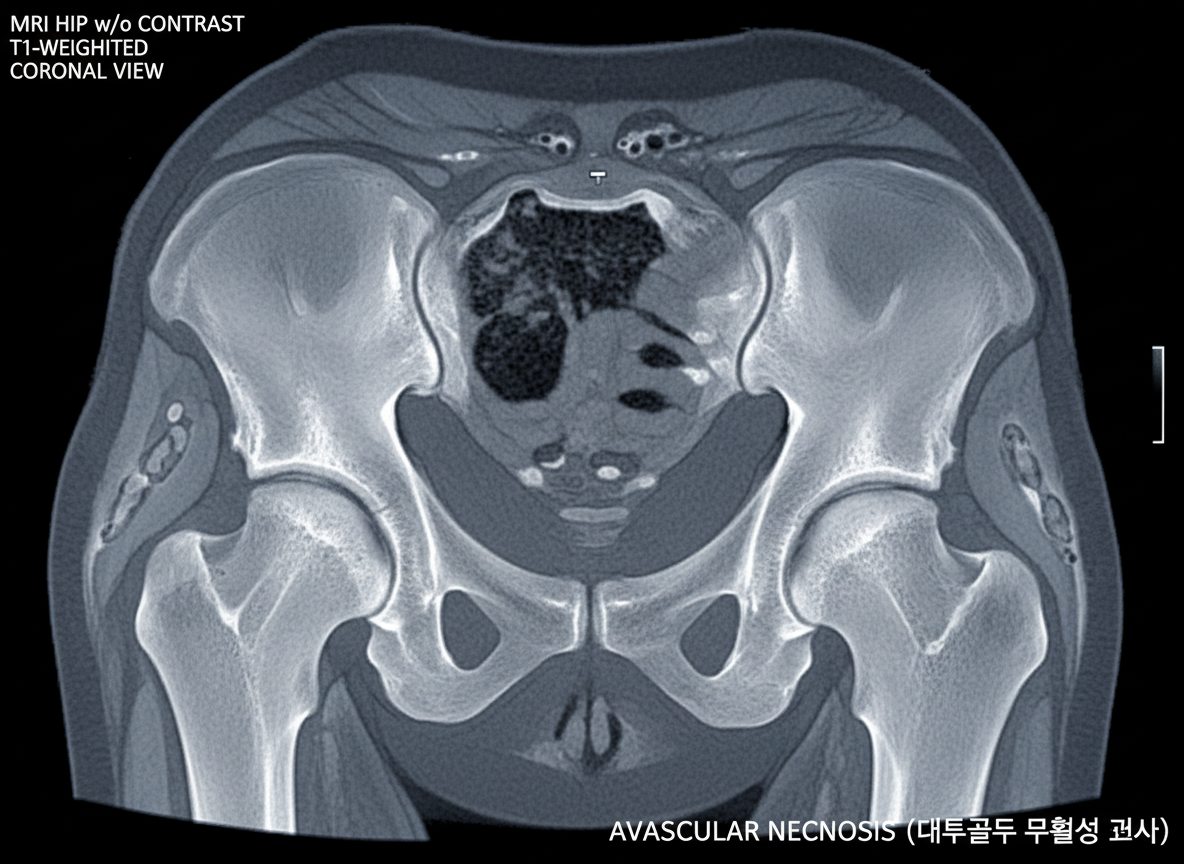

| 사타구니 통증 | 걷거나 다리 들 때, 양반다리 시 악화 | 고관절염, 대퇴골두 무혈성 괴사, 고관절 충돌 증후군 |

이런 증상들은 고관절염, 대퇴골두 무혈성 괴사, 고관절 충돌 증후군 등 다양한 질환의 신호일 수 있기 때문에, 정확한 진단을 통해 적절한 치료를 받는 것이 매우 중요해요. 통증은 우리 몸이 보내는 경고음이라는 사실을 잊지 마세요.